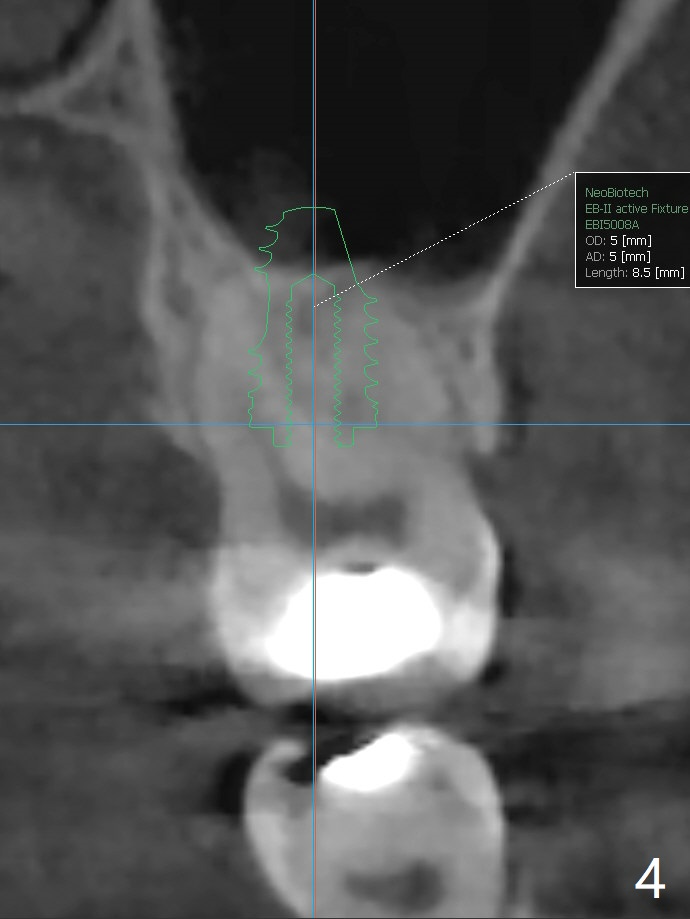

57岁女缺失2号牙多年,八年前14号牙折裂,根管治疗失败,改为即种(徒手),上颌骨骨质高度不足(图一),植体就一定植入上颌窦?近来15号牙又怀疑折裂,不愿接受根管治疗,要求种植。其实14号牙植体植入腭侧牙槽窝,顶端还有骨质,根尖颊侧多个螺纹似乎没有骨质覆盖,但是没有症状。15号牙上端上颌窦膜薄(图三),如果提升时窦膜完整,植入5x8.5毫米植体(图四),否则放置PRF,胶原塞,可以不植骨,植入5x7.3毫米植体(图五)。